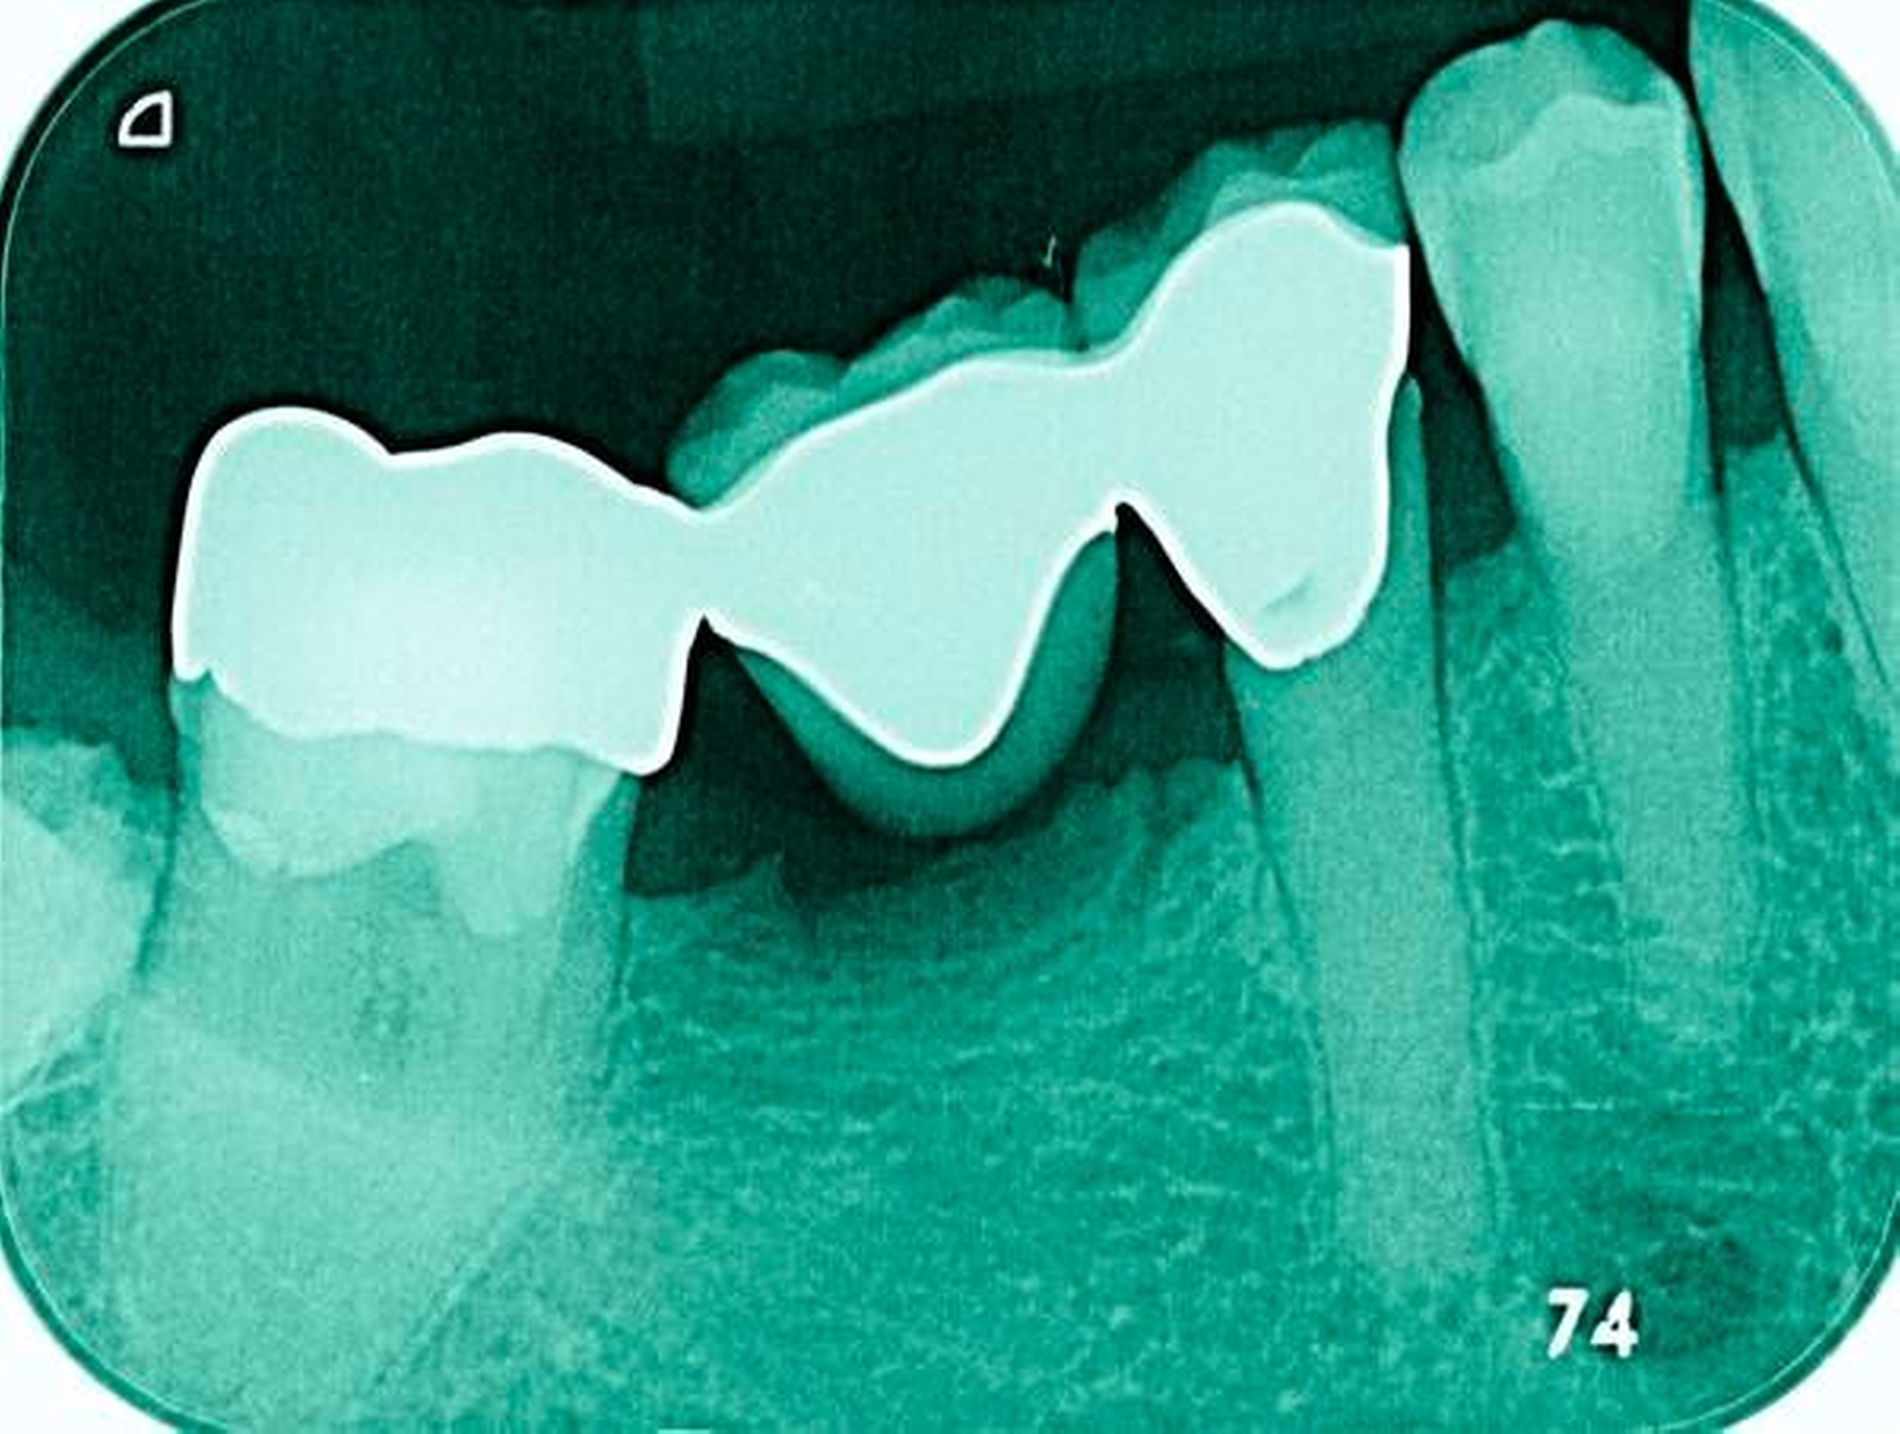

Abbildung 3: ausgedehnte Kronen- und Wurzelkaries unter einer Krone am Pfeilerzahn 47 einer seit Jahrzehnten eingegliederten Brücke von 45–47 bei einer 71-jährigen Patientin, die nach einer zerebrovaskulären Erkrankung unter Antikoagulantientherapie steht, vor etwa zwei Jahren hat sie eine Umstellung auf eine fluoridfreie Zahnpaste vorgenommen.

3. Restaurative Versorgungen bei Wurzelkaries

Freiliegende Wurzeloberflächen können im Alter ein locus minoris resistentiae für Karies sein. Im Zusammenspiel ungünstiger Ernährungsgewohnheiten, nachlassender Mundhygiene sowie Änderungen von Speichelquantität und -qualität kommt es zuweilen zu einem präventiv und restaurativ schwer beherrschbaren Auftreten von Wurzelkaries. Gut zugängliche Kariesläsionen können mit einphasig eingebrachtem Komposit (R1-Restaurationen) angegangen werden (Abbildungen 3 bis 5). Bei schwerer zugänglichen Arealen kommt ein zweiphasiges Vorgehen in Betracht (R2-Restaurationen). Das Vorgehen bei der R1- und bei der R2-Technik wurde mehrfach beschrieben [Frese et al., 2014a, b, c, d; Staehle et al., 2014, 2017]. Im Fall von zirkulärer Wurzelkaries sollte frühzeitig eingegriffen werden, da ansonsten die gesamte Zahnkrone frakturieren kann.